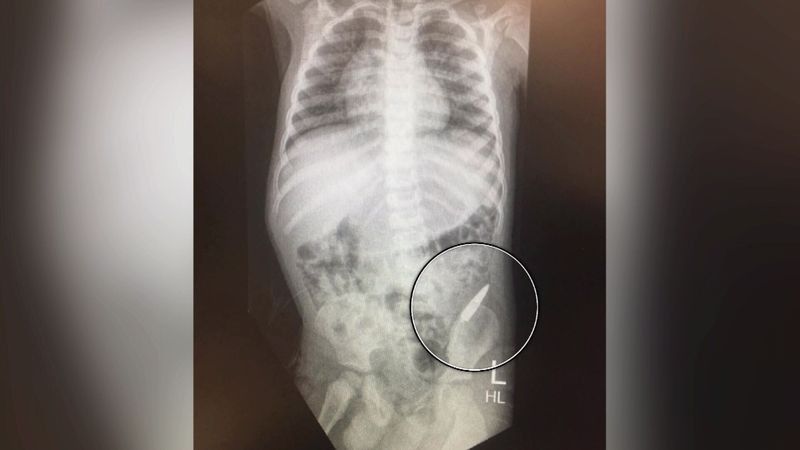

Sidoqoftë, ai është dërguar me urgjencë në spital, ku pas rëntgenografisë së bërë është konstatuar se plumbi ka ngecur në zorrën e trashë. Megjithatë plumbi nuk ka shkaktuar kurrfarë dëmi, kështu që mjekët nuk kërkuan ndërhyrjen kirurgjikale.